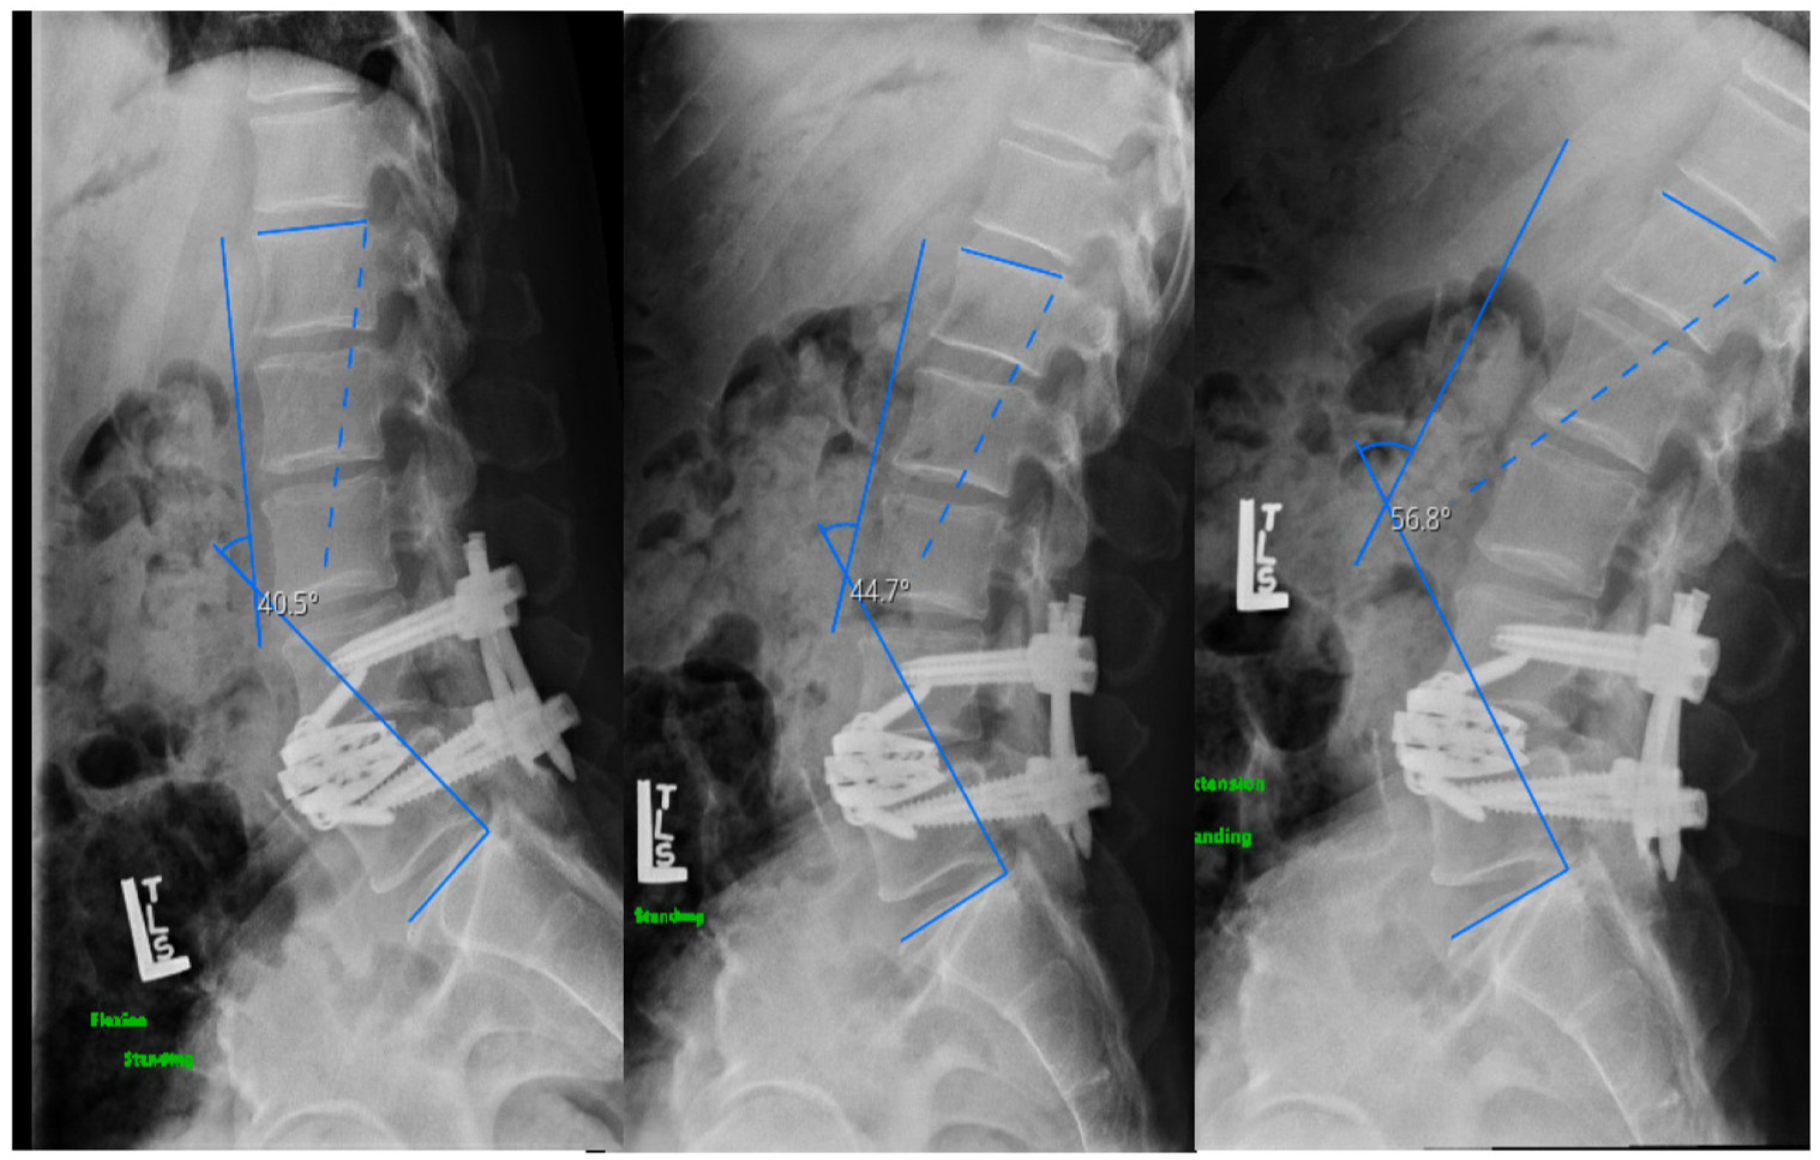

2.4.1. Case I

2.4.2. Case II

2.4.3. Case III